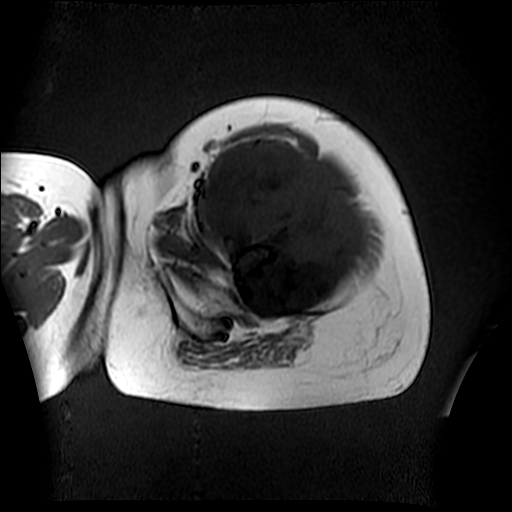

左侧大腿外伤10余年,当时情况不清,发现左侧大腿肿胀7年余,而后又有多次外伤史,近1年来出现疼痛,减重半年。查体:左侧大腿肿胀明显,皮温、肤色正常。

软组织肿块,股骨破坏,增强不均匀强化-----支持恶性肿瘤